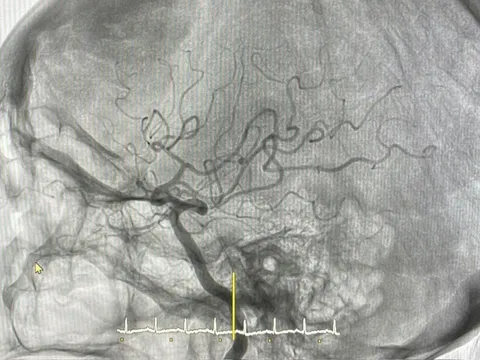

Tại đây, khi tiến hành chụp chiếu và làm các xét nghiệm, các bác sĩ phát hiện trẻ còn có tình trạng viêm phổi rất nặng, đông đặc, lan tỏa toàn bộ 2 bên phổi.Cứu sống bé trai 9 tháng tuổi 3 lần ngừng tim

Sau 2 giờ vào viện, trẻ rơi vào tình trạng suy hô hấp, suy tuần hoàn kèm theo phù phổi cấp, trào bọt hồng lẫn máu qua đường thở. Bệnh nhi ngay lập tức được đặt ống nội khí quản, thở máy và áp dụng các biện pháp cấp cứu, hồi sức tích cực. Tuy nhiên, sức khỏe của trẻ không cải thiện, tình trạng nhiễm khuẩn vẫn tăng nhanh kèm theo suy đa tạng nặng, suy hô hấp cấp tiến triển nguy kịch. Bệnh nhi ngay lập tức có chỉ định siêu lọc máu liên tục để điều chỉnh các rối loạn thăng bằng kiềm toan.

Ths.BS Cao Việt Hưng, Trưởng khoa Hồi sức tích cực-Chống độc cho biết, trong đêm điều trị đầu tiên, tức là khoảng 6 giờ sau khi trẻ nhập viện, có những lúc các bác sĩ tưởng chừng không giữ được bệnh nhân khi có tới 3 lần trẻ bị ngừng tim, mặc dù chúng tôi đã dùng các biện pháp hỗ trợ tối đa nhất. Mỗi lần như vậy, các y bác sĩ đều phải thực hiện ép tim cho trẻ từ 30-45 phút thì tim mới đập trở lại, tuần hoàn mới được tái lập và tình trạng huyết áp của trẻ mới dần ổn định.